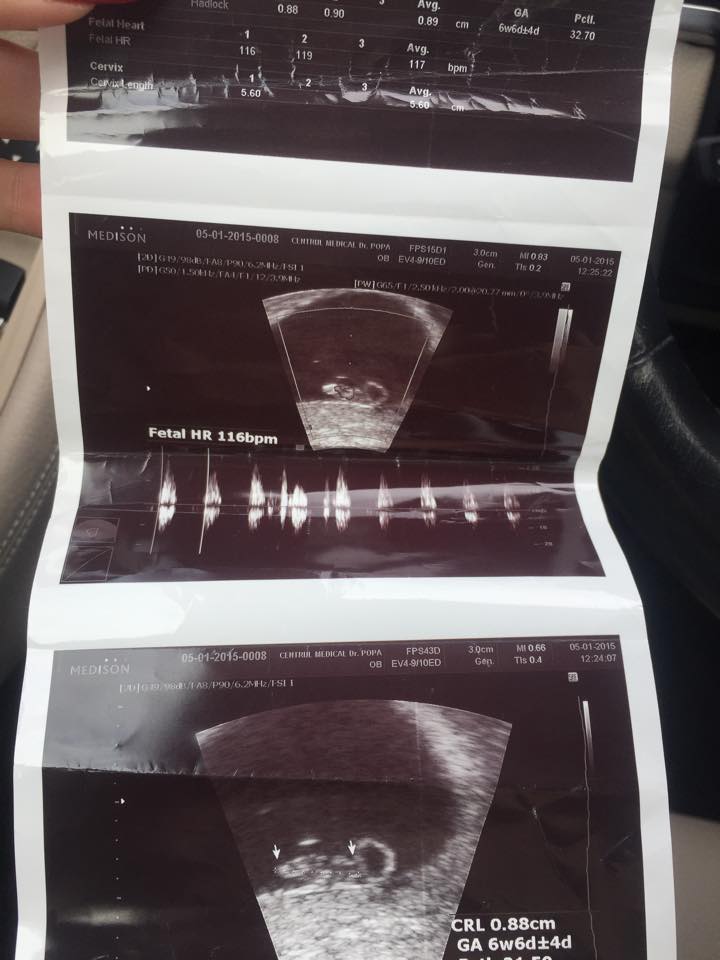

“Am aflat ca sunt insarcinata pe 25 decembrie, iar doctorii spun ca voi naste pe 15 august, chiar de Sfanta Maria. Va fi un baietel, asta am aflata cum doua saptamani. Nunta si botezul vor fi pe 27 septembrie 2015, iar cununia civila acum in mai.

“Suntem foarte fericiti ca o sa avem un copil, asta ne-a maturizat si ne-a legat mult mai mult! Acum nu ne gandim decat la el si asteptam cu nerabdare sa treaca de fiecare data cele trei saptamani sa mergem sa-l vedem. E sanatos, cuminte si timid!

Cu greu si-a aratat sexul, isi tinea mana sa nu vedem. Nu era planuit, dar il doream. Burtica inca nu am, a inceput sa se formeze putin dar e mica. Primele doua luni de sarcina mi-a fost foarte rau, dar de trei saptamani ma simt mai bine”, ne-a spus in exclusivitate Bianca Jurca.